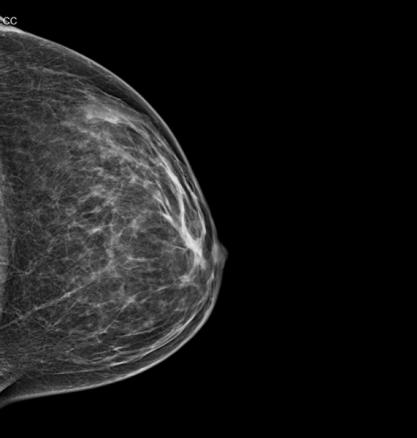

Tumeurs du sein - Mammographie normale, densité type 2

mammographie

Cliché de face.